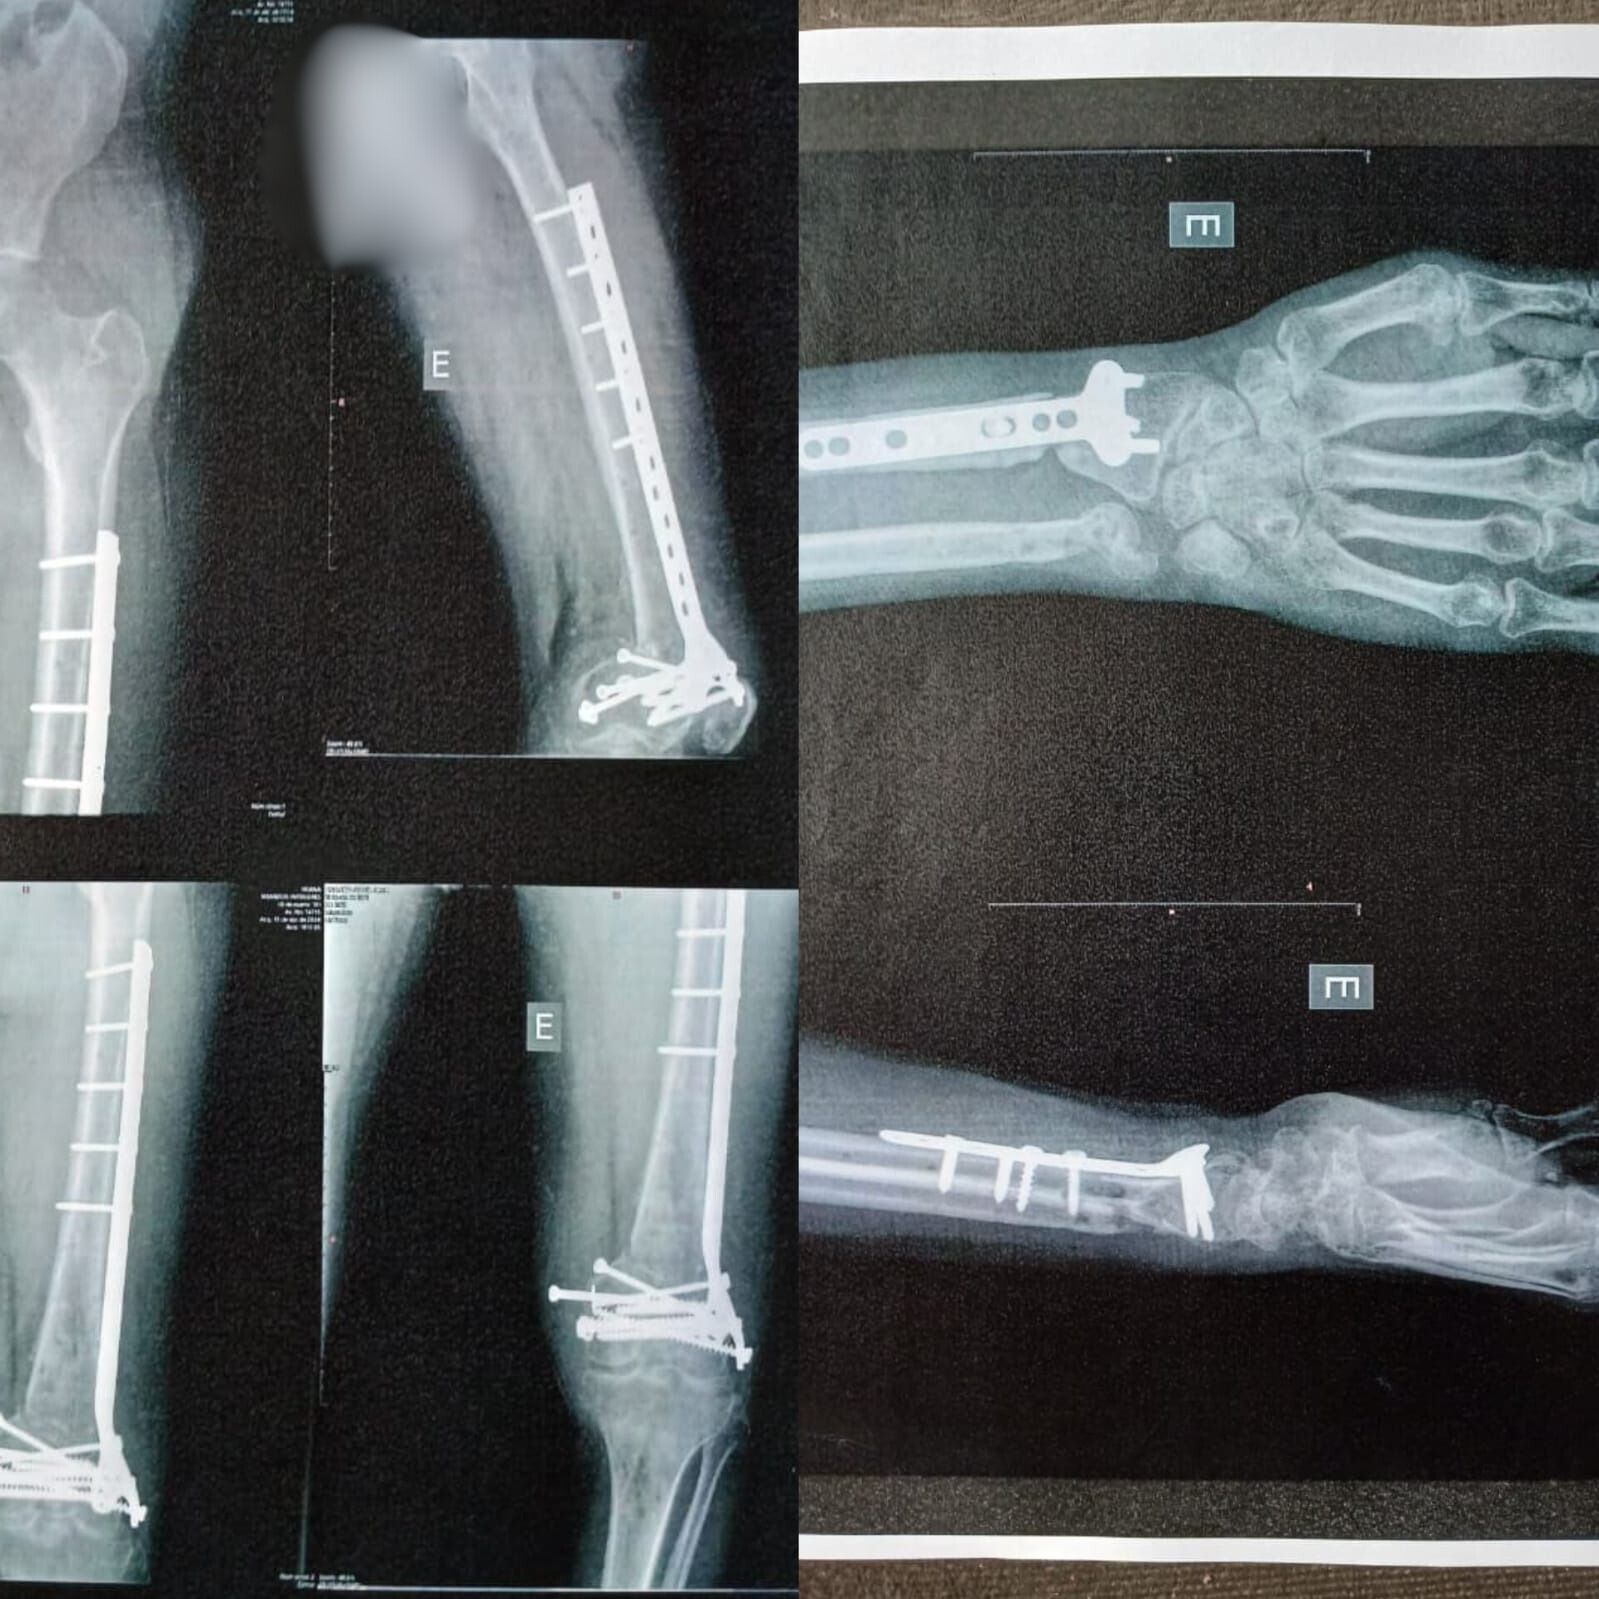

Toda essa luta e os diversos “bicos” sofreram um doloroso e quase fatal revés em novembro de 2023. A caminho do trabalho em sua motocicleta, Adriano foi atropelado por um caminhão.

O acidente resultou em diversos ossos quebrados, perda de parte do nariz e um coágulo na cabeça. Com uma das pernas esmagada e permanentemente paralisada, ele não pôde mais seguir com a vida ativa que levava.

“Faço tratamento até hoje por conta das sequelas, mas assim que me recuperei o suficiente, perguntei ao meu médico se poderia pelo menos trabalhar com aplicativo para não ficar totalmente parado. Ele autorizou, e investi em um veículo automático por causa da perna”, relembrou.